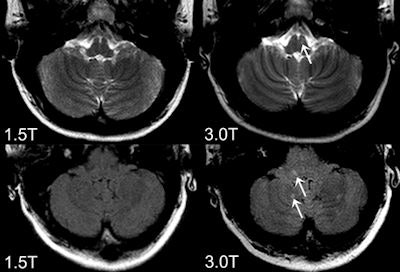

Axial FLAIR (bottom) and T2-weighted images (top) obtained at 3-tesla (right) and 1.5-tesla (left). The 3-tesla MRI shows more an inflammaory lesion in multiple sclerosis patients in the posterior fossa, which is clincially highly relevant because infratentoral lesions play an important role in the current diagnostic criteria and do have predictive value in terms of long term disability. All images courtesy of Dr. Mike Wattjes.The high standard of clinical trial methodology for drug testing is not transferable when comparing one diagnostic imaging method with another. Technological improvements occur continually, and it is impossible to systematically compare each new technique with an existing one, they explained. Only major steps require validation, and the discussion of the diagnostic benefit of higher magnetic field strength will shift gears when whole-body ultrahigh field MR systems operating at 7-tesla need to be compared with 3-tesla.